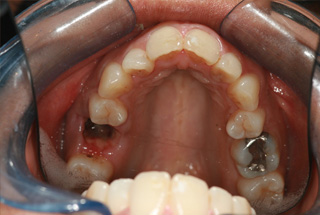

London Dentist Invisalign Braces Before

Before

Please scroll below for some of our past Invisalign cases: